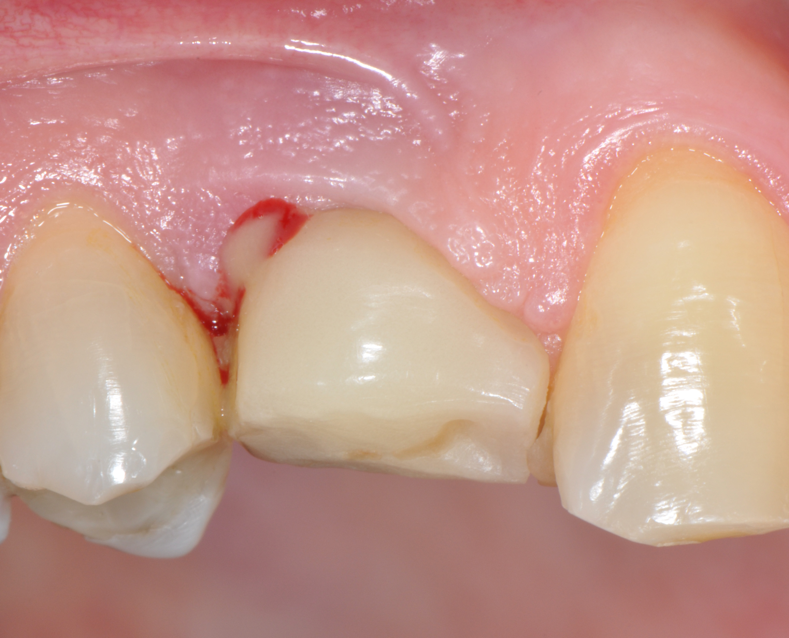

Fig.10: Case 1. Healing at 6 months after MAINST therapy. PPD has decreased to 2mm. BOP and suppuration are absent.

So far, there is no scientific evidence supporting the efficacy of this coadjuvant. The tested protocol consist of a Multiple Anti Infective Non Surgical Therapy (MAINST) that involves the use topical 14% doxycycline to solve the peri-implantitis acute phase and, after 7 days, a session of Full Mouth Air Polishing Therapy (FM-EPAPT) through erythritol powder (Fig.7), a piezo-ceramic device with a PEEK tip (Fig.8), the curettage of internal pocket line (Fig.9) and a second application od Doxy. The patients were further followed with quarterly maintenance sessions carried on with the same FM-EPAPT protocol. Up to 12 months BOP and mean PD decreased significantly and successfully, accompanied by a gain of attachment level up to 12 months. The first case-series about MAINST is waiting to be published and the results are encouraging. Figure 10 and 11 show the healing at 6 and 12 months after MAINST protocol of the peri-implantitis case displayed at the beginning of this article (Fig.1,2,3,4) and figure 12-21 show a complete MAINST case.